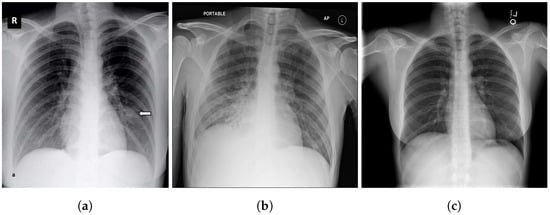

4.5. Explainability

- Selvaraju, R.R.; Cogswell, M.; Das, A.; Vedantam, R.; Parikh, D.; Batra, D. Grad-cam: Visual explanations from deep networks via gradient-based localization. In Proceedings of the IEEE International Conference on Computer Vision, Venice, Italy, 22–29 October 2017; pp. 618–626. [Google Scholar]

- Panwar, H.; Gupta, P.; Siddiqui, M.K.; Morales-Menendez, R.; Bhardwaj, P.; Singh, V. A deep learning and grad-CAM based color visualization approach for fast detection of COVID-19 cases using chest X-ray and CT-Scan images. Chaos Solitons Fractals 2020, 140, 110190. [Google Scholar] [CrossRef] [PubMed]